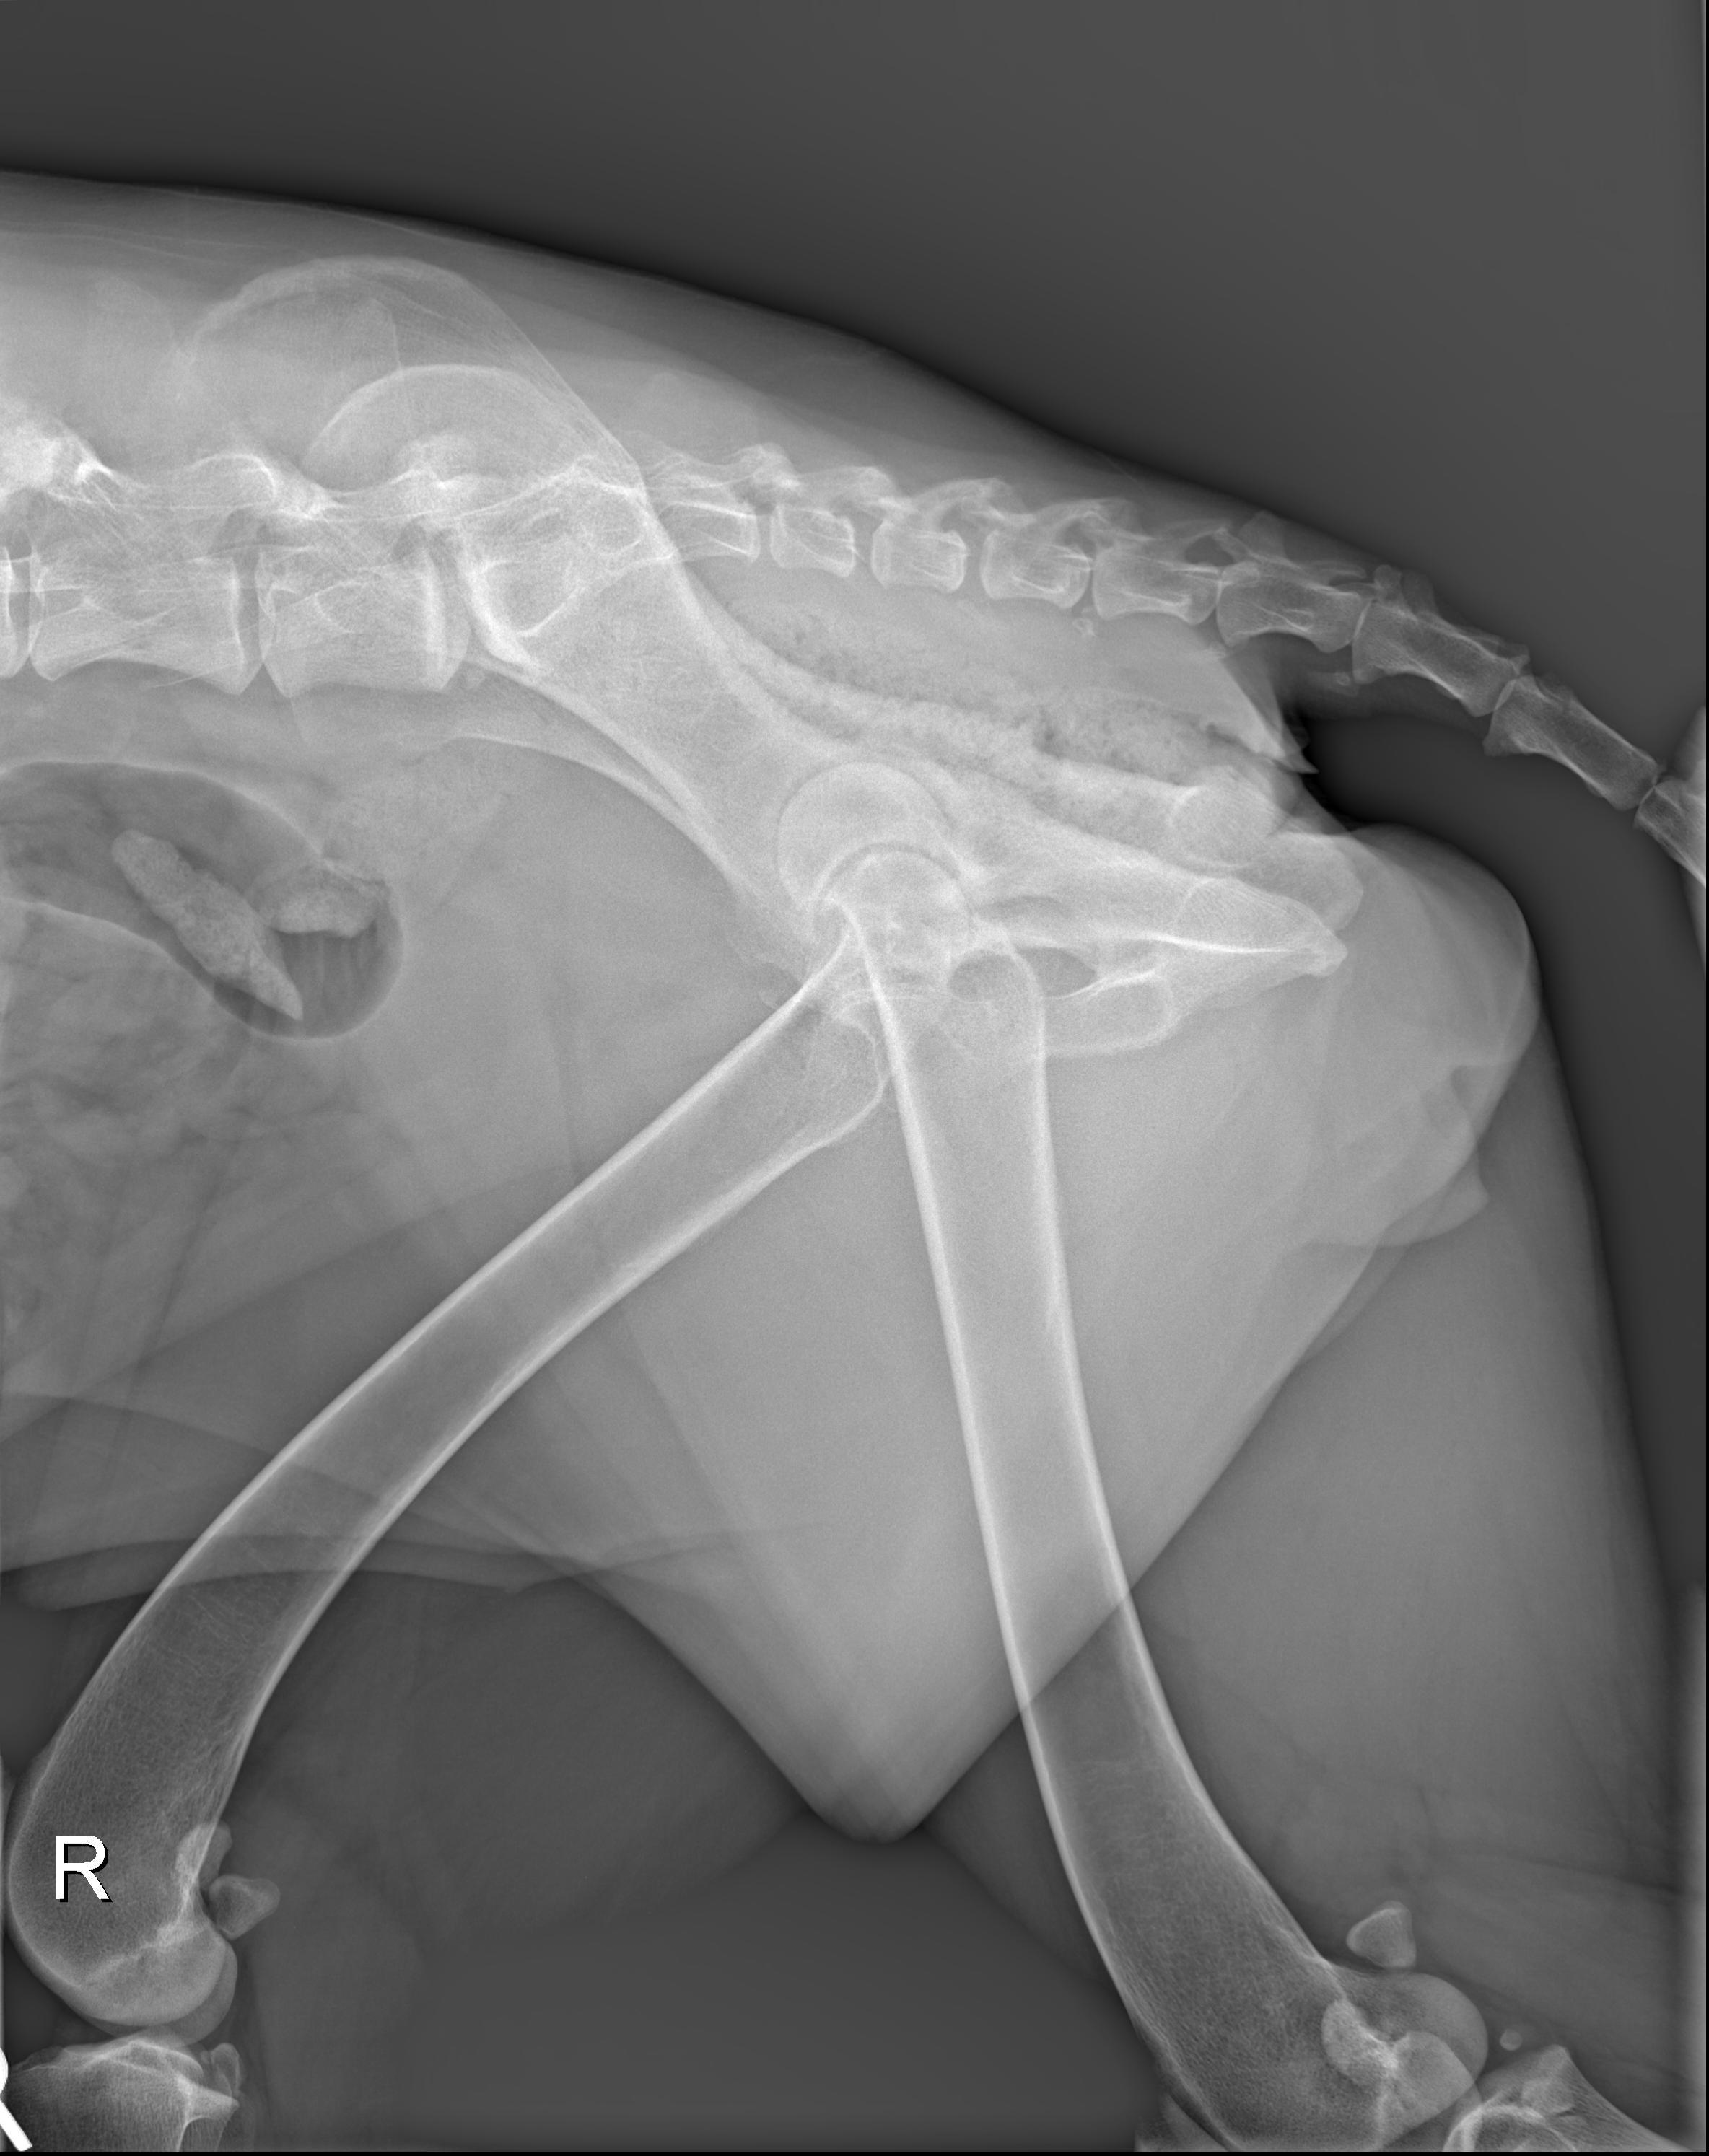

翻译:祁海丽;校对:石慧14 A 6-year-old female spayed Weimaraner (Figure 14.1) was given a c...